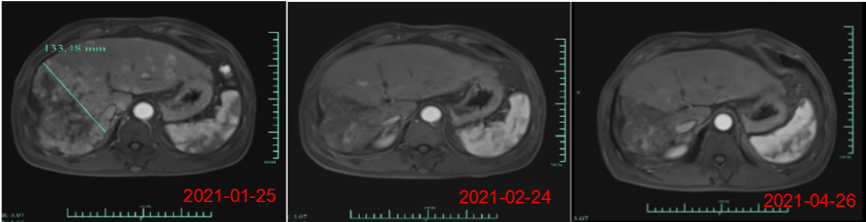

杨焕凤表示,近期公司在美国临床肿瘤学会 (ASCO)发表了核心产品Ori-CAR-001在治疗难治复发型肝细胞癌的探索性临床研究数据,截至三月份,在9例可评估数据中,有4例获得PR(部分缓解),截止到目前,受试者007的缓解周期已超过是9个月,还有一例受试者012的PR缓解周期已达5个月,其肿瘤缩减的幅度接近93%。

此外,最近的一个新的爬坡剂量的首个患者也获得了PR(自ASCO数据发布后,又新增了一位部分缓解的病人)。目前,这些病患目前仍在持续随访中。“在晚期实体肿瘤治疗中,这个缓解时间还是相当长的,肿瘤减小的幅度也是非常惊人的,这个结果令团队很受鼓舞,我们期待在进一步的产品开发和临床研究过程中,获得更好的数据。